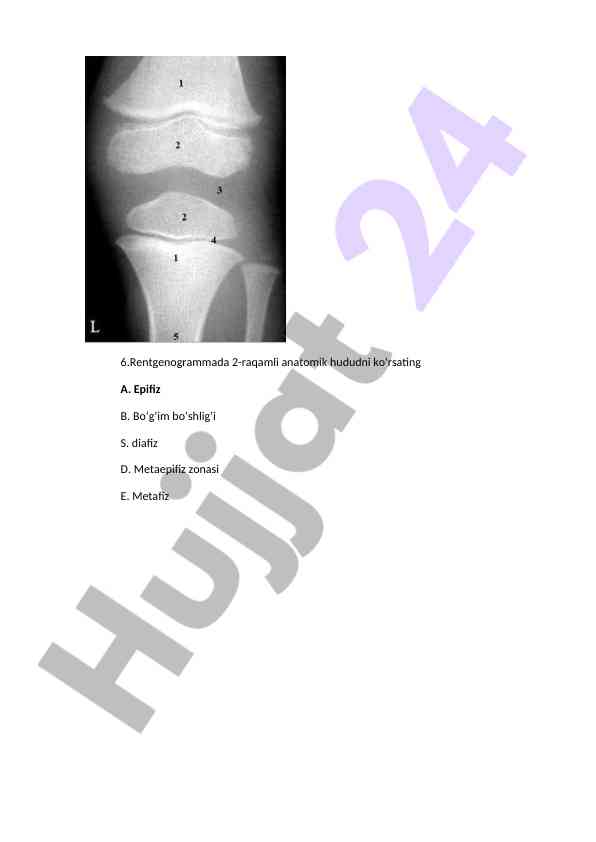

Rentgen tasvirlari bilan bog'liq diagnostik savollarga oid maslahatlar va javoblar, tibbiyotda rentgenografiya qo'llanilishi haqida ma'lumotlar.